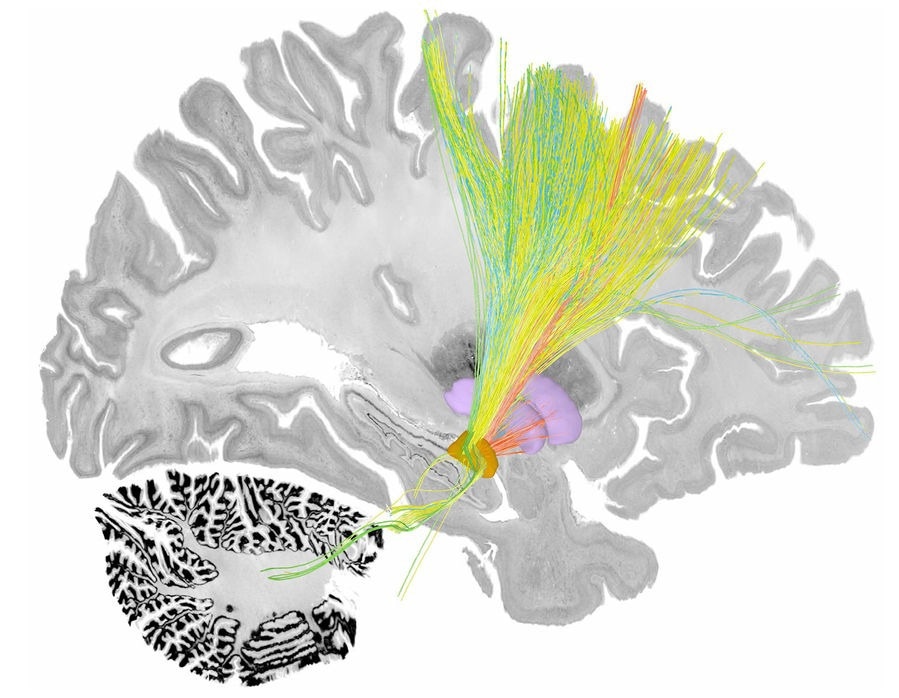

Brain circuits associated with symptom improvements of tremor (green), bradykinesia (blue), rigidity (red) and axial symptoms (yellow) following deep brain stimulation to the subthalamic nucleus (orange). The pallidum is shown in purple. The backdrop shows a sagittal slice of the BigBrain dataset. Image credit: Nanditha Rajamani

The researchers from Mass General Brigham studied a total of 237 patients with PD who were treated with DBS to identify tracts associated with four major PD symptoms: tremor (uncontrolled movement), bradykinesia (slow movement), rigidity (freezing), and axial symptoms (such as gait and posture irregularity or instability). With software developed by Horn’s team, the researchers pinpointed the precise location of DBS electrodes in each patient and created a common map of the circuits associated with patients’ symptom improvement. Tremor was shown to improve with stimulation of tracts connected to the primary motor cortex and cerebellum, while bradykinesia was associated with the supplementary motor cortex. Rigidity was shown to improve with stimulation of the premotor cortex.

Axial symptoms, which have not received extensive study in relation to DBS, improved with stimulation of tracts connected to the supplementary motor cortex and brainstem. This finding may be especially important given that axial symptoms, such as gait or postural stability problems, typically do not respond well to DBS and existing dopaminergic therapies, such as levodopa.